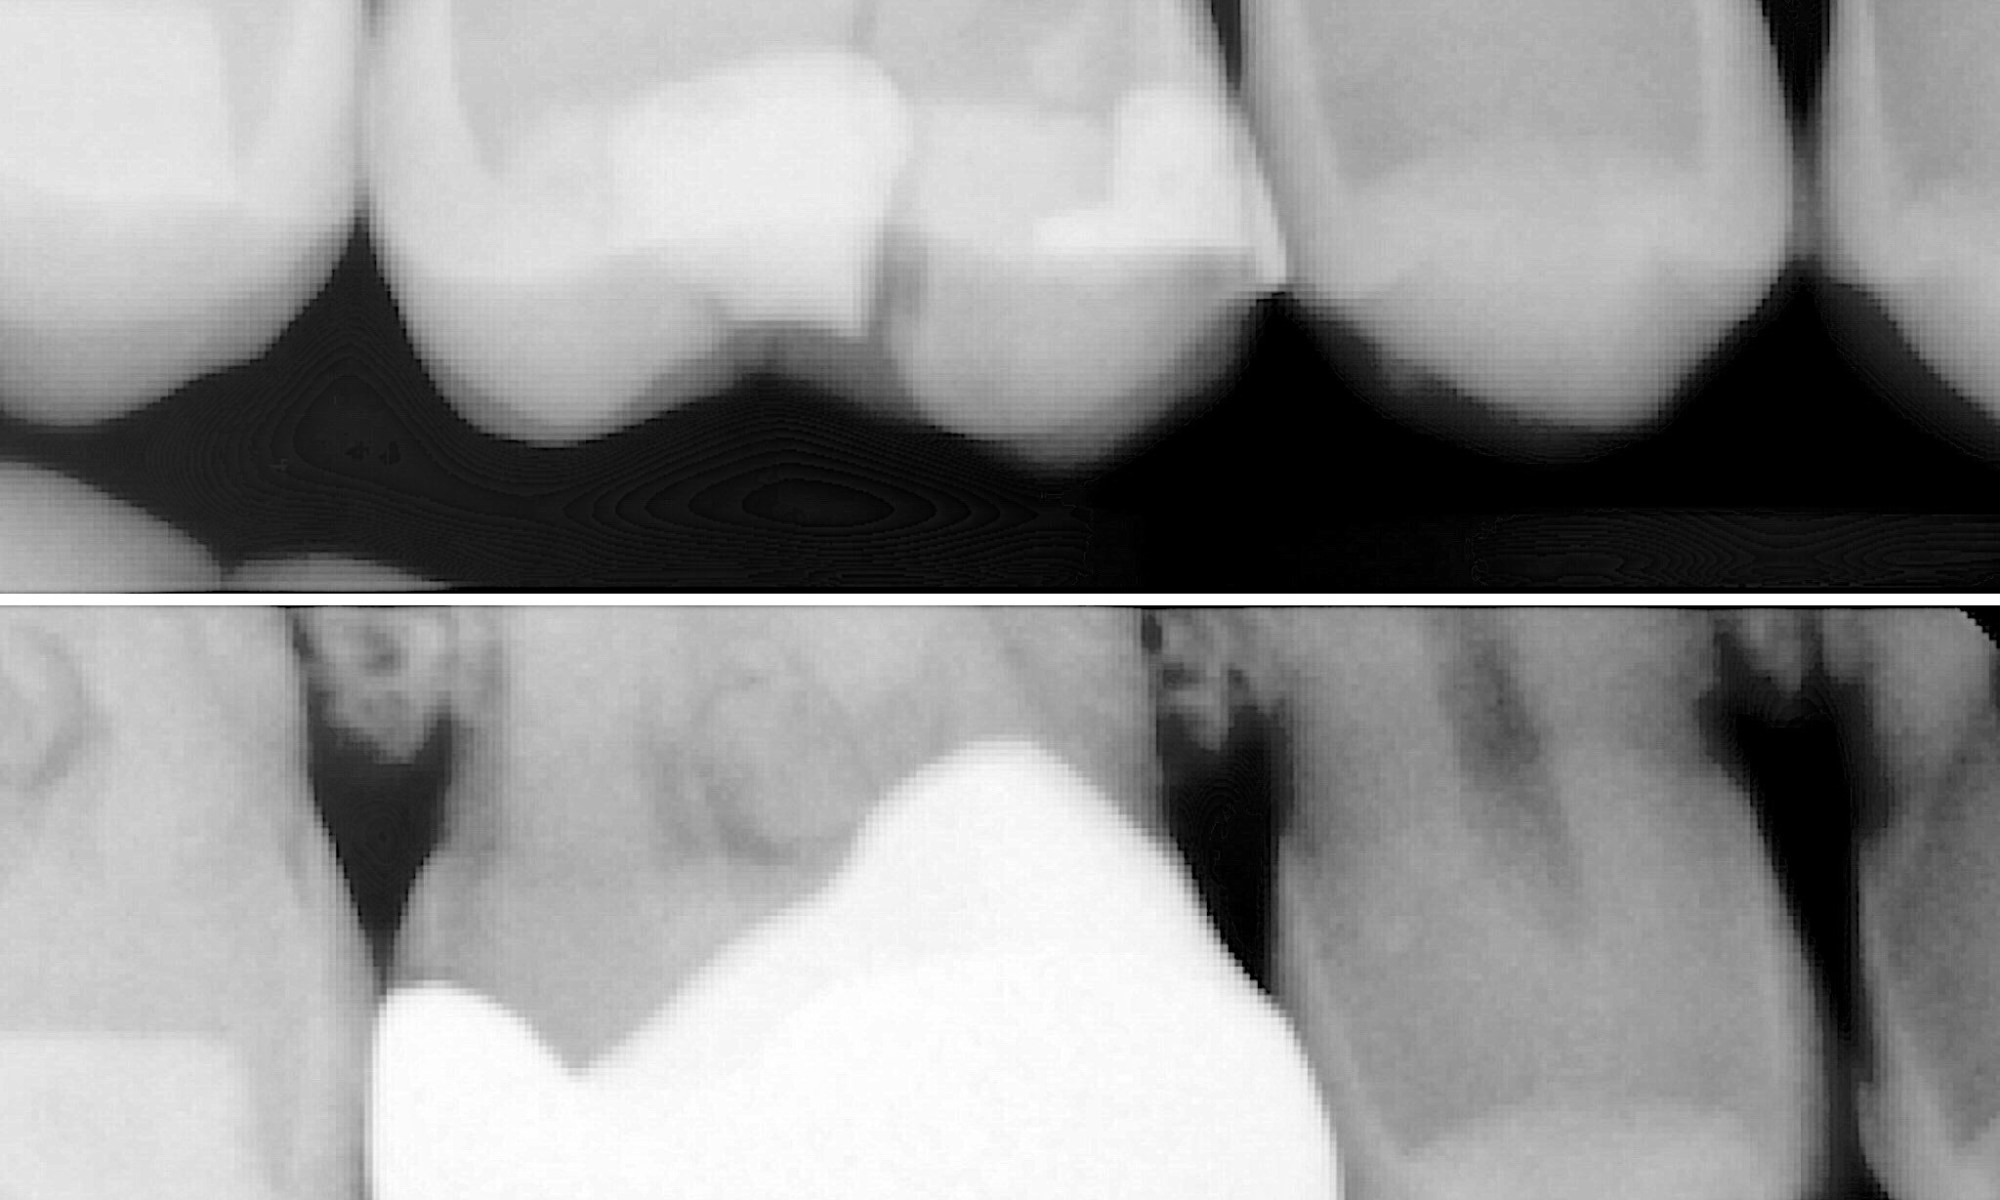

Can you spot the vertical fracture very close to the pulp chamber? This was corrected with full zirconia crown. Happy patient.